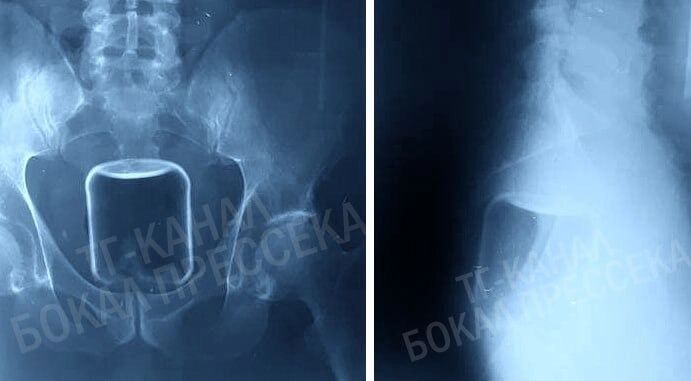

Банка

Житель региона обратился за помощью после неудачного интимного эксперимента. В его кишечнике застряла стеклянная банка объемом 0,5 литра. Хирурги действовали максимально осторожно, чтобы стекло не треснуло. Пациента удалось спасти, и он покинул больницу в удовлетворительном состоянии.